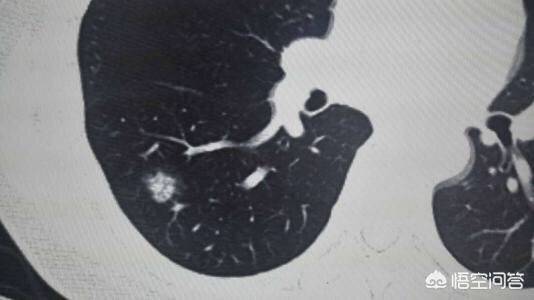

肺结节通俗的讲就是CT上黑色的肺里有小白点。直径大于3cm一般称为肺部肿块,肺癌的可能性相对较大。通常我们将直接小于3cm的圆形或者椭圆形占位病变称之为孤立性肺结节,它被肺实质包围,完全没有相关的淋巴结肿大、肺不张或肺炎。直接小于2cm的称为肺内小结节,直接小于5mm的称为微小结节。

如何判断肺结节是良性还是恶性呢?1.结节的位置:肺癌更多发生于上叶,尤其好发于右肺,但肺结核留下的一些疤痕结节也饿多发于上肺,所以要注意鉴别。2.结节的形态:胸部ct被公认为是鉴别肺部小结节良恶性的最佳检查手段。假如CT上描述有深分叶、短粗毛刺、空泡征、空气支气管征、胸膜凹陷征、肺血管集中征以及明显的强化征等,都认为是恶性征象,千万不可懈怠。如果结节边界光滑,钙化位于病灶中央或为层状、弥漫性和爆米花样则多见于良性病变,结节内有脂肪多见于良性的错构瘤等。3.结节的大小:直径小于5mm,恶性的可能性很小,大约在1%以内;5~10mm时,恶性可能性为6%—28%;直径大于20mm的肺结节恶性概率达到80%。